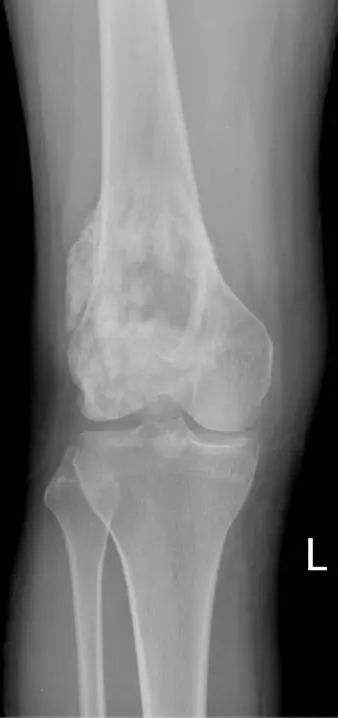

本題提供左膝關節正位(AP)及側位(lateral)X 光片兩張(標記「L」):

正位片(AP view):

- 股骨遠端可見大範圍破壞性骨病灶,累及幹骺端(metaphysis),向骨幹方向延伸

- 病灶呈**混合性溶骨-硬化(mixed lytic-sclerotic)**型態,骨小梁結構破壞

- 可見侵略性骨膜反應(aggressive periosteal reaction),包含典型的放射狀骨刺(sunburst pattern)——新生骨以輻射狀從皮質向外延伸

- 皮質(cortex)明顯被破壞,腫瘤突破皮質形成大型軟組織腫塊(soft tissue mass)

- 骨膜被抬起處可見 **Codman 三角(Codman triangle)**徵象